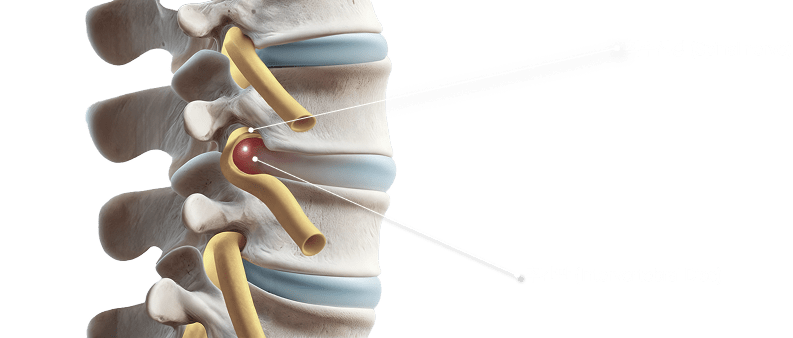

도침 치료를 통해

협착증 통증을 유발하는

조직의 압력을 해소합니다.

초음파 진단 기기를 활용하여 척추 주변 인대 조직의 비후,

골극 형성, 연부 조직의 병변 상태를 정밀하게 확인할 수 있으며

도침 치료를 통해 신경압박을 유발하는 원인을 치료할 수 있습니다.

01. 도침

도침 치료는 침 치료의 확장된 형태로 협착증과 같은 구조적 문제를 동반한

통증 질환 치료에 큰 도움이 되는 치료법입니다. 일반 침보다 굵고 편평한 형태의

침으로 근막, 인대, 유착된 연부조직 사이를 물리적으로 박리할 수 있습니다.